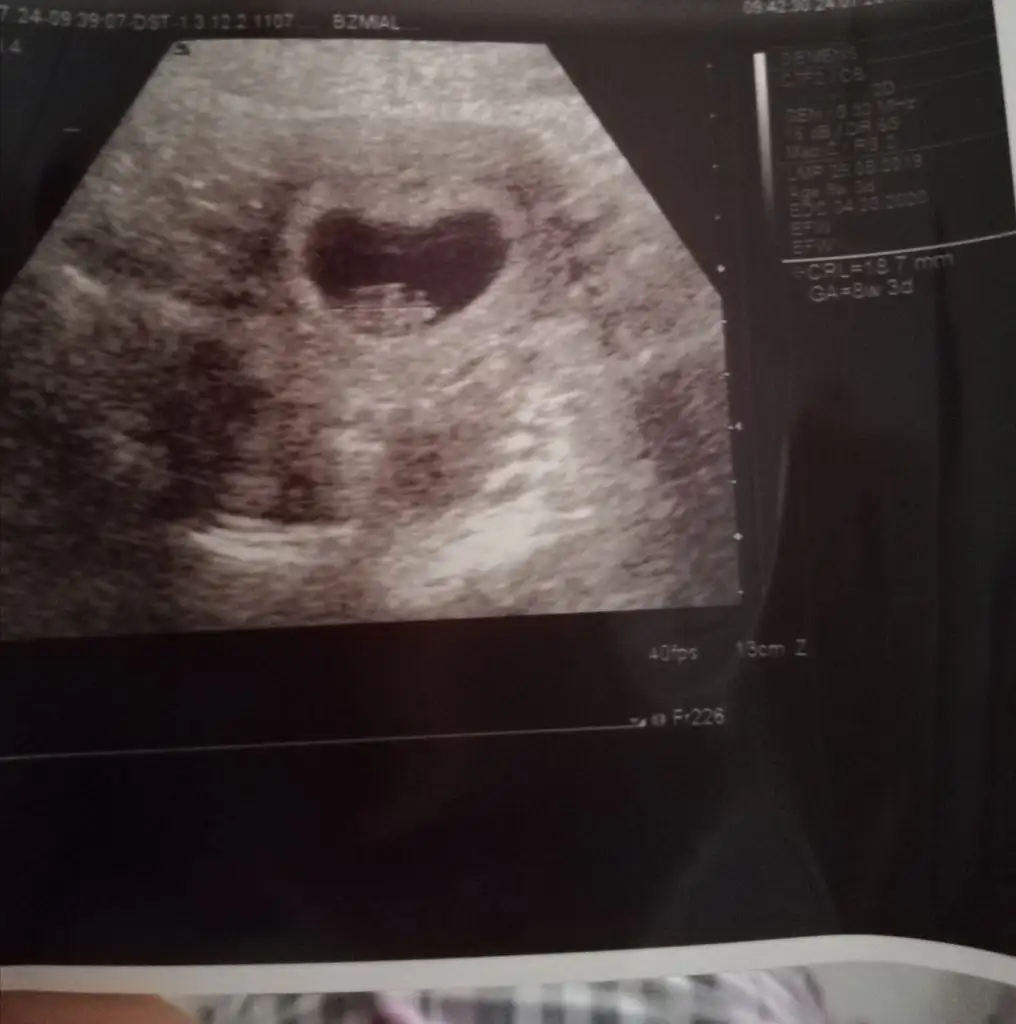

Bu arada kızlar bugün hastaneye gittim. Takvimime göre 8+0'dı tam bugün. 6 haftalıkken kalp atışını duymuştum. Bugün farklı bir doktora gittim kese, kalp atışı, boyu herşeyin çok güzel olduğunu. Haftasıyla uyumlu olduğunu söyledi. Ultrason kağıdında 8+3 yazıyor clr ama oda normal heralde. Bebişimin boyu 18.7 mm. 2 hafta öncede kalp atışını dinlemiştim üst üste dinlemek inşallah zarar vermez bebeğe bazıları sakıncalı demiş çünkü. Doktor bana birşey söylemedi.

İçimde büyüyen bir kalp var kanıtıda burda :)) kesem tam kalp gibi değil mi? :)) fasulyeye benziyordu geçen haftalarda ama bu hafta kalp gibi olmuş artık.

Bebeğin kalbinin attığını, böyle vücudunu hareket ettirdiğini gördüm ultrasonda gerçekten çok güzel bir duygu. Rabbim herkese bu duyguyu yaşatsın. Sağlıkla kucağımıza alalım inşallah.